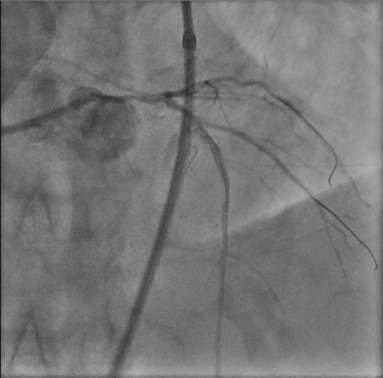

As patient is having cardiogenic shock from a LM occlusion and refusal of CABG, a high-risk, mechanically-supported PCI was undertaken. An IABP was inserted via the left femoral artery for hemodynamic support.Right femoral artery approach. 7Fr EBU 3.5 Guide. LAD and LCx were wired with microcatheter support. 2.0 balloon was used to predilate the LM-LAD lesion, TIMI 3 flow restored.IVUS was performed, showing heavily calcified plaque throughout the LM and LAD. Based on IVUS sizing (LM: 4.5mm, pLAD: 4.0mm), predilation with NC balloons followed by Intravascular Lithotripsy (IVL) with a 3.0 Shockwave balloon for 70 cycles were performed.A 2.75/40mm DES was placed in the mid-LAD and a 3.5/24mm DES was deployed from the ostial LM into the proximal LAD. POT in the LM using a 4.5 NC balloon, followed by post-dilation of the proximal LAD with a 4.0 NC balloon.Post-angiography revealed a jailed D1 with TIMI 0 flow. Rewiring to D1 was reattempted successfully with a CTO wire. Switched back to workhorse wire, dotted and predilated with 1.5 semi-compliant balloon. However IVUS showed wire likely true-false-true with ostial D1 in subintimal. Decided not to further intervene on D1.Final IVUS showed satisfactory results. Angiogram after adenosine showed regained flow in D1, TIMI 3 flow in both LAD and D1. Patient remained hemodynamically stable on IABP support post-procedure.

Case Summary